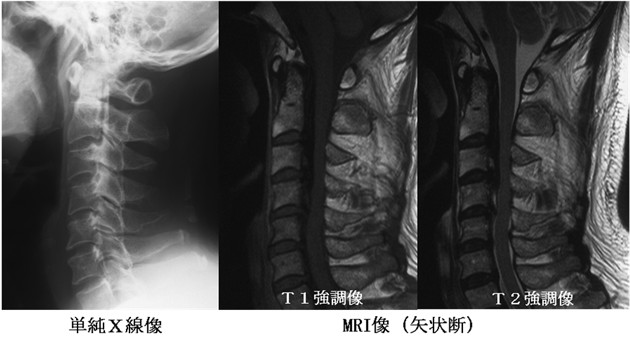

単純X線検査、CTで靭帯の骨化を認めれば頚椎OPLLと診断されます。また、MRIによって脊髄の圧迫の程度を評価することもできます。